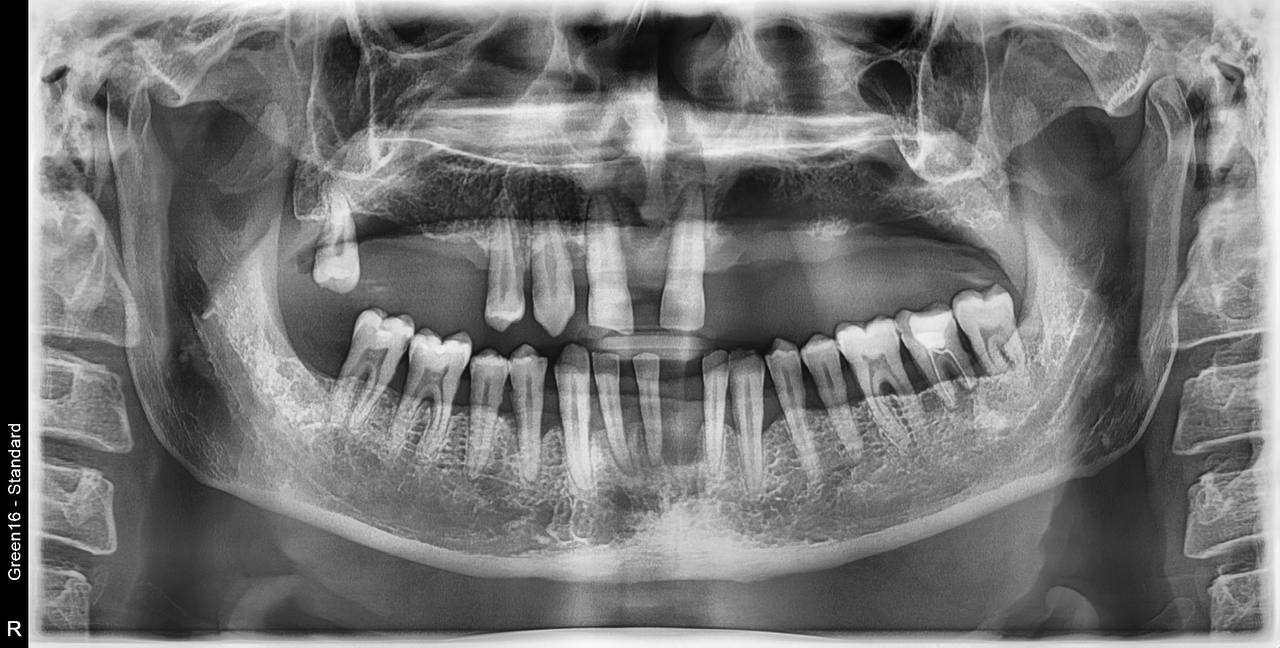

All on 4

Zdjęcia wykonanych zabiegów